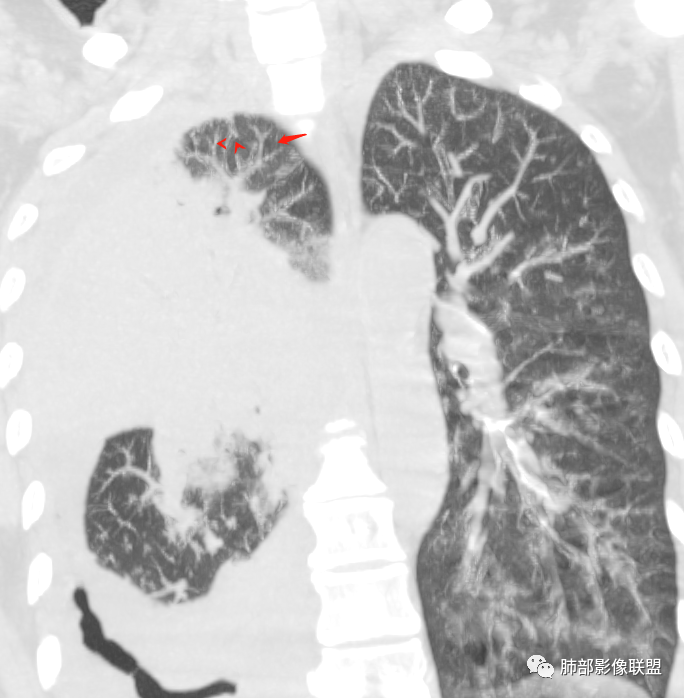

为啥给的视频支气管扩张明显啊!似乎有树芽征,如果确实是树芽征,结核要考虑。

那就结核放首位,鹦鹉热其次;支气管、树芽征符合;还是要警惕结核,肺链不支持。

单纯PPT的图像我考虑鹦鹉热。但是给的视频,明显支气管远端扩张。

问个问题:这是啥?空洞?扩张支气管?

感觉像是扩张的支气管,不确定

该病例,需要二元解释,这么高的白细胞提示感染,这个病例确实很怪。一是感染,还有淋巴瘤,一直在犹豫远端的空腔还是扩张支气管,如何形成的。这个看支气管及远端的泡。

这是扩张大支气管?还是囊腔?

空洞?

犹豫的点在于位置,与支气管关系。

一般空洞——应该在病灶的中央或实变区,这个在边缘。

囊腔?按理是近端支气管狭窄,导致气体潴留,不太符合。

因为大片实变支气管扩张原因:周围牵拉,支气管壁破坏。

这个在边缘,周围没有牵拉等因素,所以应该是壁的破坏。

壁破坏,这样的就需要观察整个壁的形态。

病灶本身占位效应,边缘膨隆,边缘没有收缩的迹象,也就是说支气管周围没有牵拉的因素导致其扩张,我们只能考虑支气管本身导致的扩张。

1、结核类的慢性炎症——狭窄、扩张、扭曲;

2、神经、肌肉破坏,导致支气管收缩不理想——光滑、通畅、远端扩张;这一类——淋巴瘤.

从支气管的改变:要警惕淋巴瘤。左肺病变沿支气管血管束分布,支持间质为主病变。

这也是我判断失误的原因之一:树芽征

重建后就是血管束增粗

我以为树芽征,其实是中轴间质增厚

没看清楚,只看到表面,考虑小气道结节,那些是支气管扩张+空洞,所以考虑结核,其实两点都错了,谢谢赖老师。

应该要二元.看这样的支气管。